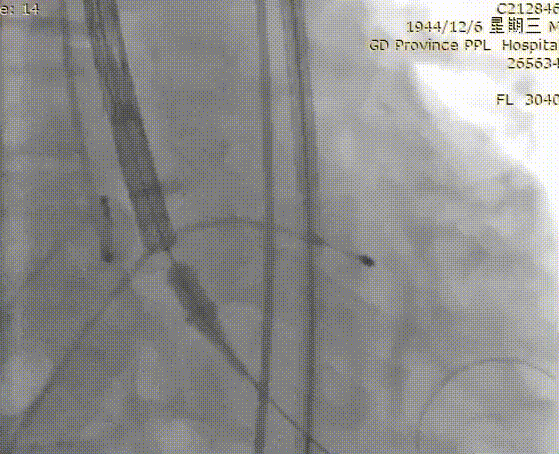

VitaFlow®可回收输送系统过弓

24 mm球囊预扩

VitaFlow®第一次定位

释放2/3后造影确认位置

回收后再次定位

再次造影确定位置

释放瓣膜

球囊后扩